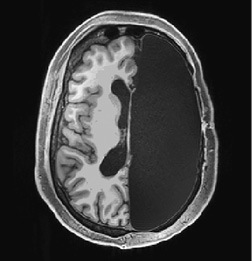

На протяжении нескольких часов хирург кропотливо удалял нежную розоватую мозговую ткань, составлявшую основу интеллекта Мэтью, его эмоций, способности говорить, чувства юмора, страхов и привязанностей. Извлеченная ткань, бесполезная в отрыве от своей биологической среды, отправлялась в маленькие контейнеры. Опустевшая половина черепа Мэтью медленно заполнялась спинномозговой жидкостью, что в ходе нейровизуализации отображалось черным пятном (рис. 1.1)[3].

Рис. 1.1. У Мэтью хирургически удалена половина головного мозга

Источник: Kliemann D., et al. (2019). Intrinsic functional connectivity of the brain in adults with a single celebral hemisphere. Cell Reports. 2019 Nov 19; 29 (8): 2398–2407. © 2019, with permission from Elsevier